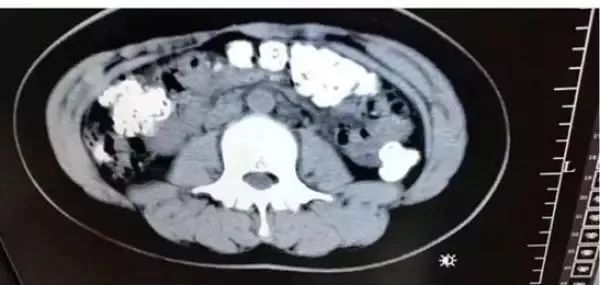

CT检查发现胃肠道

布满一颗颗圆圆的高密度阴影

——没有消化的“珍珠”

接诊医生张楼炜见她肚子鼓鼓的,便安排了腹部CT,检查结果让他一惊:患者胃部、横结肠、升结肠、降结肠、乙状结肠,一直到肛门,全是颗粒状阴影,足有百余颗。